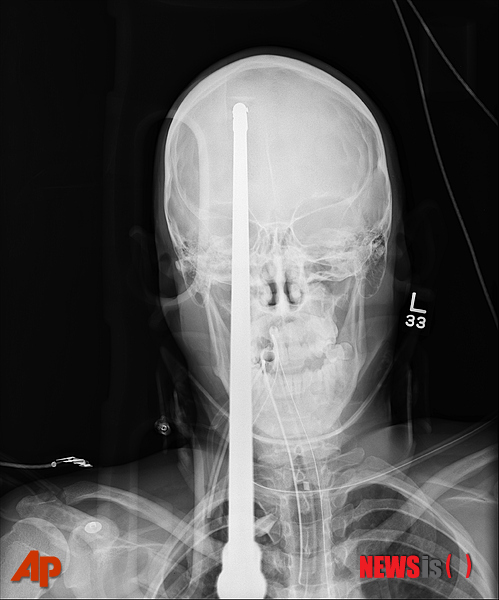

【마이애미 =AP/뉴시스】마이애미대 부설 잭슨메머리얼 병원이 19일 공개한 작살총 맞은 소년의 사진. 야세르 로페스라는 이 소년(16)은 한 친구가 우연히 발사한 작살총에 맞아 작살이 끼워진 채로 병원에

실려와 치료를 받았으나 위독한 상태다.